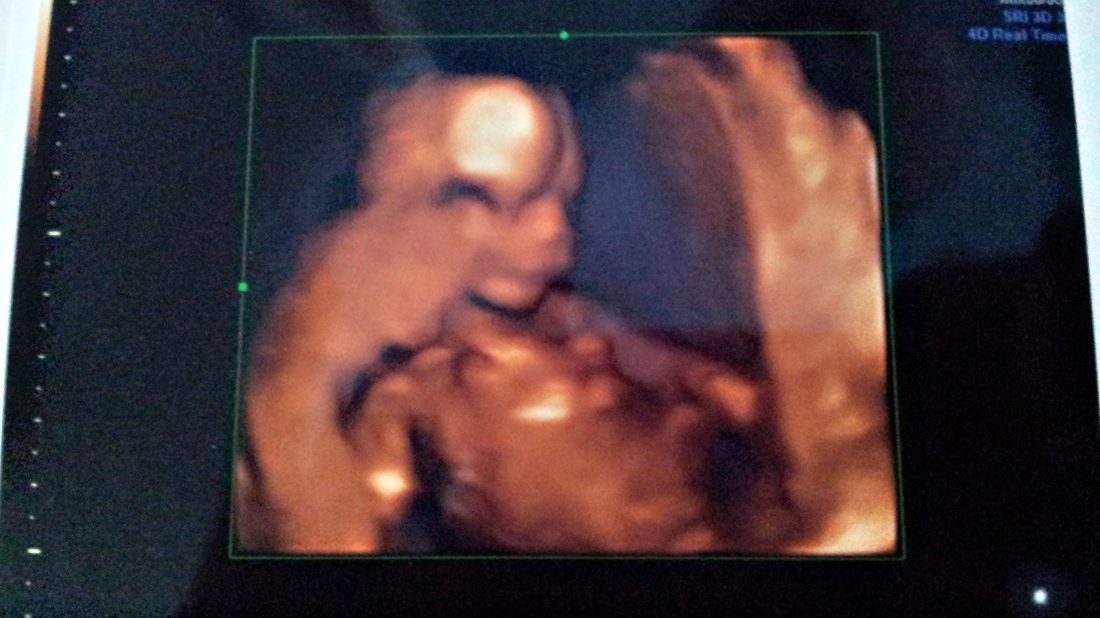

Paní doktorka byla moc příjemná a trpělivá – tak moc nám chtěla vyjít vstříc a ukázat nám naše mimi v celé kráse, ale náš červík se rozhodl, že nám ukáže záda – a to doslova. :o) (Páteř má teda opravdu hezkou, to se musí nechat.) Klidně si tam ležel na boku, zády k nám – ukázal nám aspoň pravou ručku se všemi prstíky a po pár minutách se rozhodl protáhnout si nožku. Bylo to hrozně srandovní, roztomilé a úžasné. Paní doktorka se ale nevzdávala – rozhodla se, že nám pořídí aspoň trochu ucházející obrázek a tak mi jezdila po břichu a hledala nějaký vhodný úhel, při kterém by se jí podařilo zachytit obličejík. Červík si s námi ale hrál na schovku za placentou – v jedné vteřině ovšem vykoukl a paní doktorka ho stihla blejsknout a tak moje máma odcházela spokojeně se svou trofejí v ruce. :o)